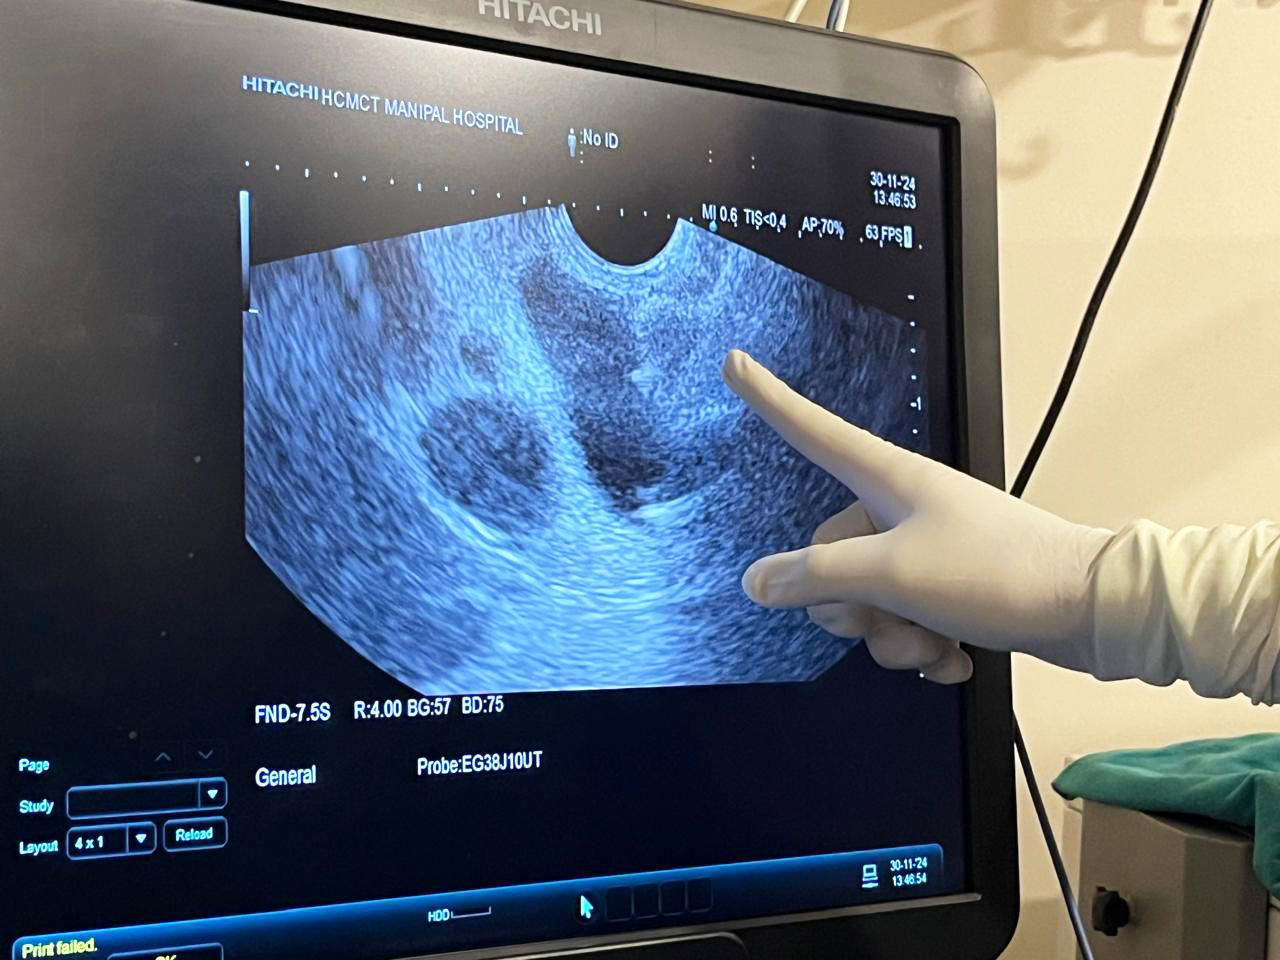

Happy to share a first for us at Manipal Hospital Delhi on 30th November: Endoscopic Ultrasound (EUS) guided Choledocho-Duodenostomy for relief of malignant biliary obstruction.

Mr SL, 68 years, was hospitalized with us for obstructive jaundice and cholangitis. Evaluation revealed growth in head of pancreas with liver mets. EUS Guided FNA with ROSE ( Rapid Onsite Evaluation) by pathologist confirmed Adenocarcinoma pancreas. At ERCP the guide-wire could not be negotiated proximal to the growth in pancreas. Such patients with failed ERCP are normally referred worldwide for PTBD(percutaneous trans-hepatic biliary drainage). We decided, instead, to access the bile duct, proximal to the obstruction, from the duodenum(D1) and with EUS guidance, place a Lumen Apposing Metal Stent(LAMS), thus establishing biliary drainage into duodenum. Procedure time was under 15 minutes and the patient is doing well.

The proximal end of the stent in dilated bile duct

Purulent bile pouring out from distal end of stent in duodenum, about 5 cm proximal to the normal opening of bile duct in Ampulla of Vater